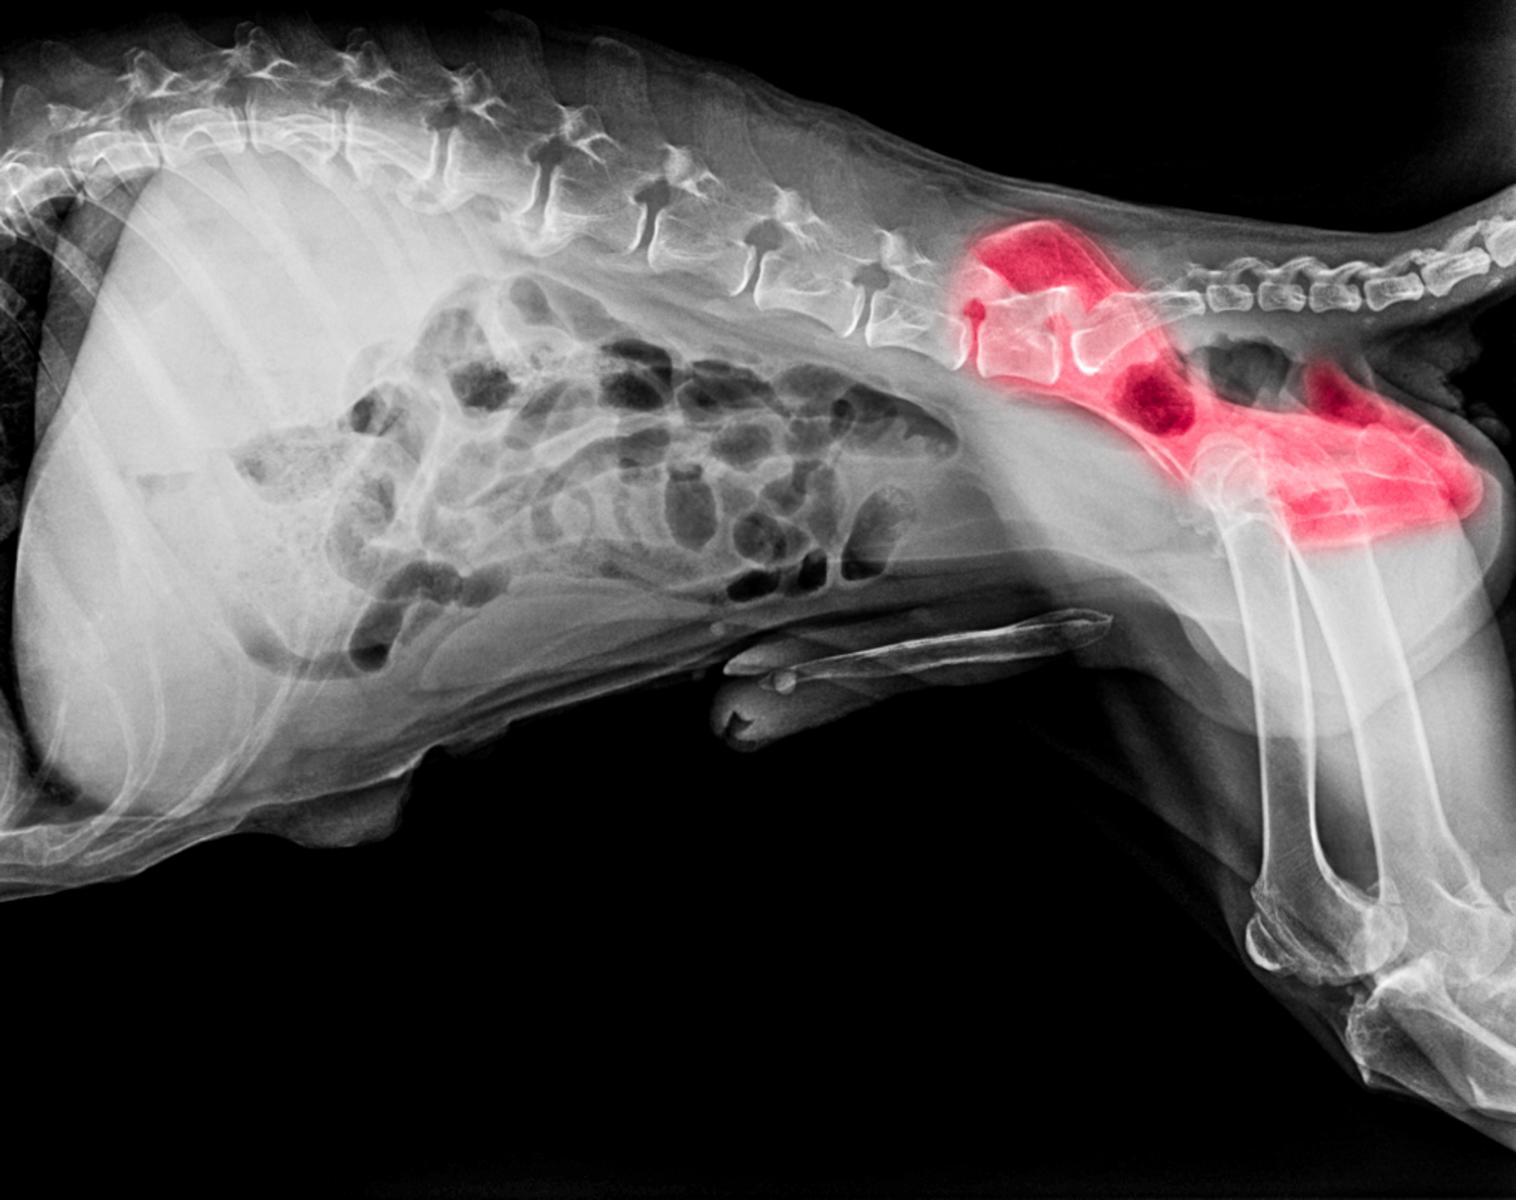

Unter einer Hüftdysplasie (HD) oder einer Ellbogendysplasie (ED) versteht man eine Erkrankung der Hüftgelenke beim Hund, welche meist erblich bedingt ist. Das Wort "Dysplasie" ist griechisch und bedeutet "schlechte Form". Leider kommt diese Erkrankung - vor allem bei größeren Hunderassen - häufig vor.

Erste Anzeichen einer Hüftdysplasie können sich zum Beispiel durch Bewegungsunlust, Lahmheit, einem breitbeinigen Gang oder Druckschmerz zeigen. Das Ausmaß der Symptome bzw. Beschwerden variiert je nach Alter, und Etwicklungsstadium der Krankheit. In schweren Fällen kann sich auch eine Arthrose entwickeln, weshalb eine tierärztliche Diagnose und Behandlung entscheiden ist.